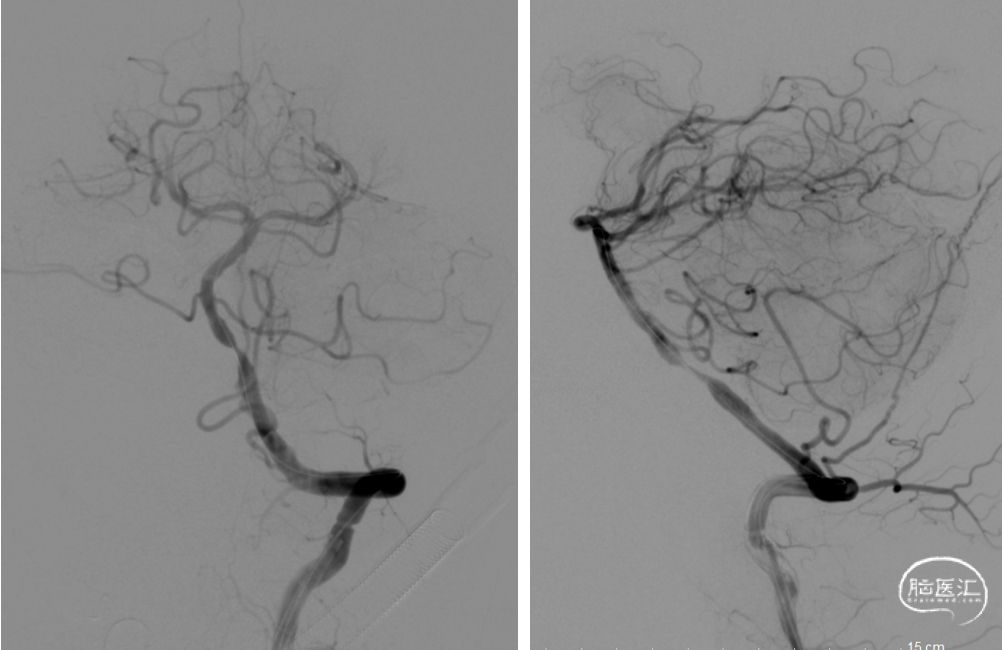

在Synchro0.014*300cm微导丝携带下将Gateway2.5*15mm球囊送至基底动脉下段狭窄处,定位准确后,以8atm压力扩张,复查造影,基底动脉下段狭窄略改善,残余重度狭窄。

撤出球囊,将APOLLO3.0*13mm支架沿微导丝送至基底动脉狭窄处,定位准确后以10atm压力释放,复查造影基底动脉显影良好,狭窄处明显改善,无明显残余狭窄,双侧大脑后动脉、双侧小脑上动脉显影良好。

Synchro0.014*300cm微导丝携带Gateway2.5*15mm球囊至基底动脉下段狭窄处,定位准确后,以8atm压力扩张,复查造影

将APOLLO3.0*13mm支架沿微导丝送至基底动脉狭窄处,定位准确后以10atm压力释放,复查造影。